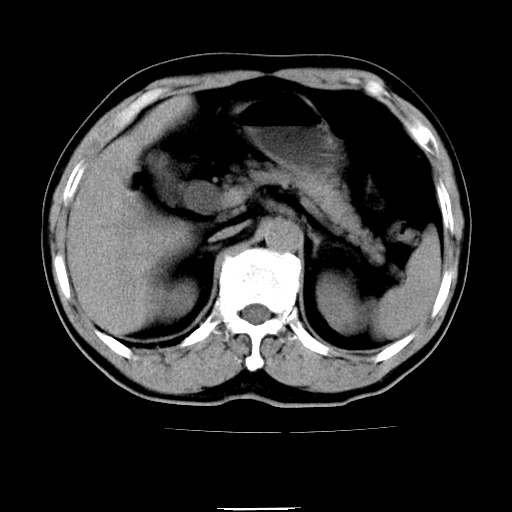

以下是引用chenqiong在2010-3-25 20:56:00的发言:[br]1、胆囊炎,胆囊息肉[br]2、肝内胆管及胆总管扩张,胆总管下端结石[br]3、十二指肠乳头旁憩室

以下是引用zxl51642在2010-3-26 10:47:00的发言:[br]胆囊炎,胆囊息肉,胆总管扩张,但未看到明显肿块,肝内胆管扩张不像恶性,炎性狭窄或阴性结石可能吧,建议mrcp,右肾小囊肿